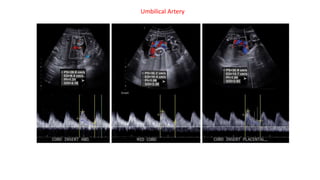

Umbilical Artery

The normal placental vascular bed is low resistance, with continuous forward flow throughout the cardiac cycle.

Diastolic flow increases as pregnancy progresses, so the S/D ratio decreases with advancing gestational age.

At 20 weeks, the 50th percentile for the S/D ratio is 4.

At 30 weeks, the 50th percentile is 2.83; and at

40 weeks, the 50th percentile is 2.18

the S/D ratio and the presence of absent or reversed end-diastolic flow are used to manage fetal growth

restriction and to stage the twin-twin transfusion syndrome.

The normal placentalvascular bed is low resistance, with continuous forward flow throughout the cardiac cycle. Diastolic flow increases as pregnancy progresses, so the S/D ratio decreases with advancing gestational age. At 20 weeks, the 50th percentile for the S/D ratio is 4. At 30 weeks, the 50th percentile is 2.83; and at 40 weeks, the 50th percentile is 2.18 the S/D ratio and the presence of absent or reversed end-diastolic flow are used to manage fetal growth restriction and to stage the twin-twin transfusion syndrome. The Doppler indices have been found to decline gradually with gestational age (i.e. there is more diastolic flow as the fetus matures): S/D ratio mean value decreases with fetal age 8 at 20 weeks, the 50th percentile for the S/D ratio is 4 at 30 weeks, the 50th percentile is 2.83 at 40 weeks, the 50th percentile is 2.18 RI mean value decreases from 0.756 to 0.609 PI mean value decreases from 1.270 to 0.967

• #6 igure 12. Umbilical vein waveforms. Top: Spectral US image shows a normal umbilical artery waveform above the line and a normal umbilical vein waveform below the line. Note the continuous flow throughout the cardiac cycle. Middle: Spectral US image shows absent end-diastolic flow (long arrow) in the umbilical artery, with undulations in the umbilical vein (*) owing to fetal breathing. The undulations are independent of the fetal heart rate. Bottom: Spectral US image shows mixed absent and reversed end-diastolic flow (short arrows) and a pulsatile umbilical vein waveform (arrowheads). The umbilical vein pulsations occur during diastole at the same time as the absent end-diastolic flow. For the best technique, sample in a free-floating loop of the umbilical cord in singletons. In multiple fetuses, sample close to the abdominal site of umbilical cord insertion to verify which umbilical vein belongs to which fetus (19). The angle of insonation is not critical, because there are no velocity measurements. Ideally, the fetus should be at rest and not breathing. Observe the shape of the waveform, and be sure to differentiate between the normal undulations seen with fetal breathing and pulsatile venous flow.